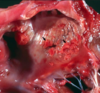

This image shows a possible sequalae of endocardiosis, name the sequalae.

What are the other 6 sequelae of endocardiosis?

Left atrial rupture (also shown here)

Others: valvular incompetency, congestive HF (R or L), atrial dilation, jet lesions, hemopericardium, chordae tendinae rupture